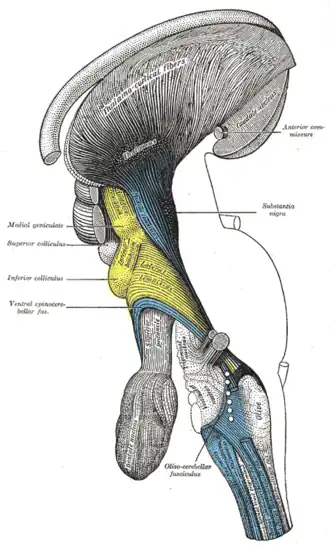

Superficial dissection of brain-stem. Lateral view.

Superficial dissection of brain-stem. Lateral view. -